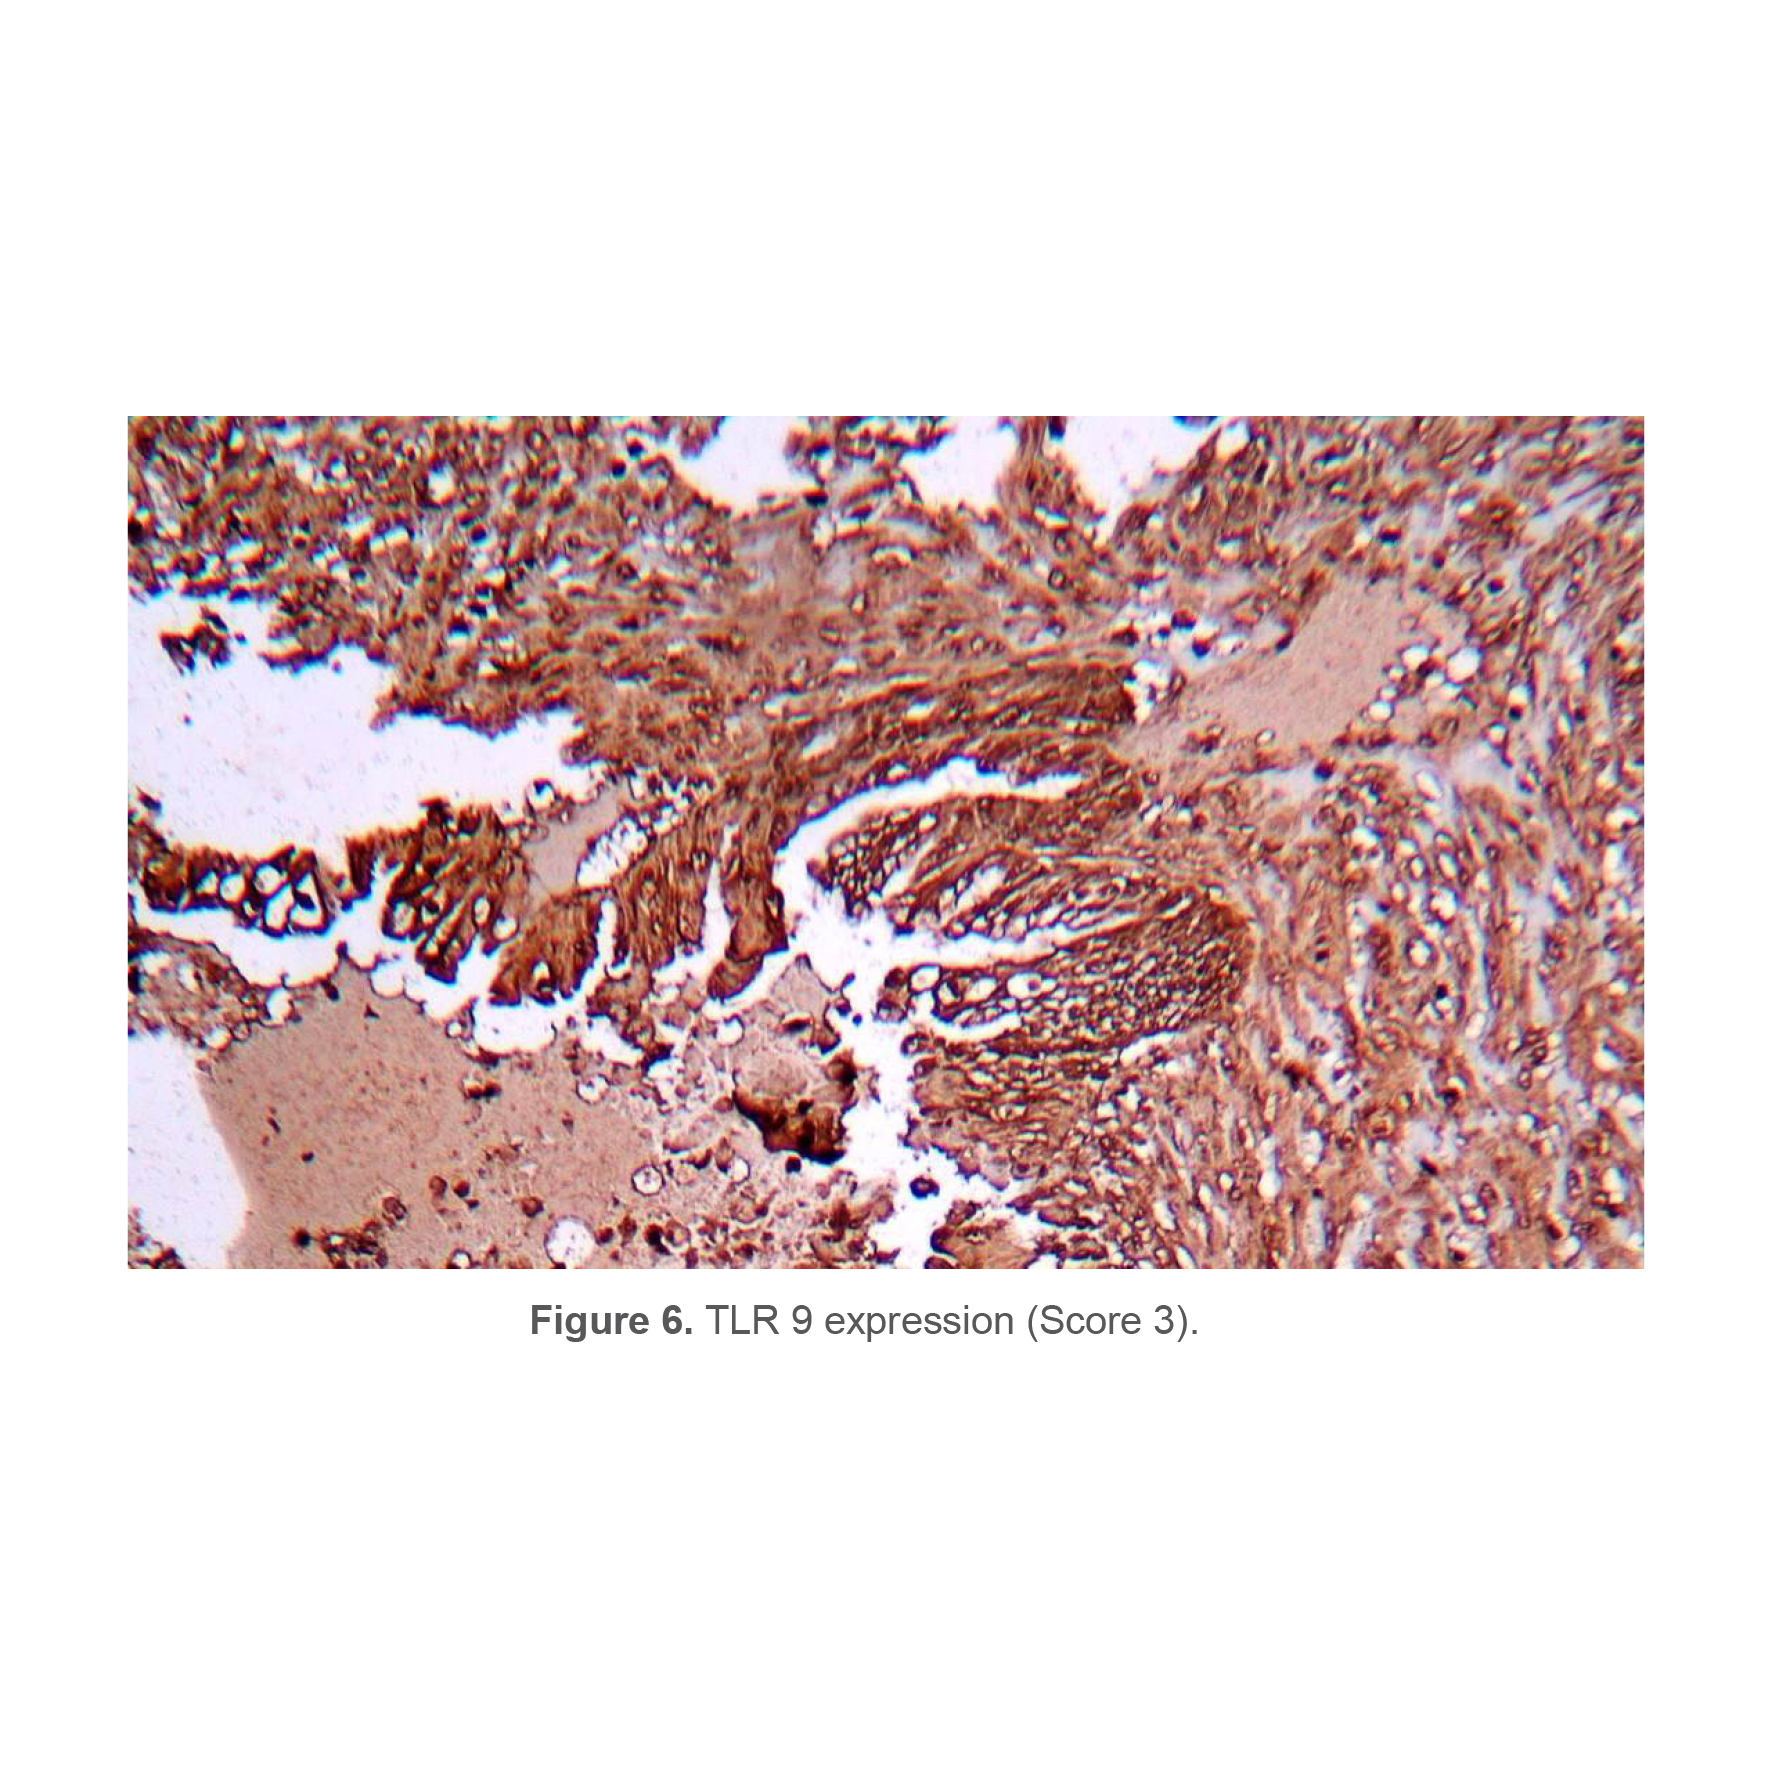

Quantitative and qualitative analysis of TRL9

Figure 6 shows the mean immunoreactivity score of TLR9. The mean IS of TLR9 in case and control was 0.19±0.48 and 0.23±0.67, respectively. No significant difference was seen between the case and control in terms IS of TLR9 (p=0.07).

Figure 6. TLR 9 expression (Score 3).